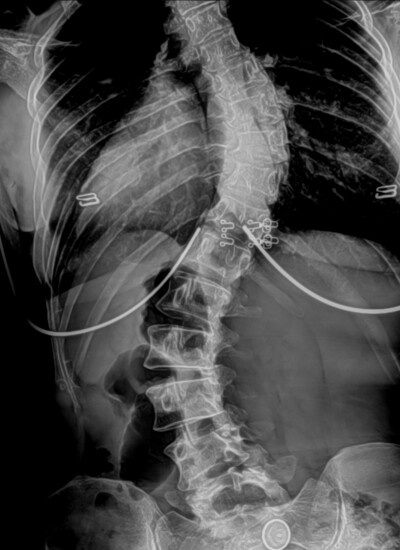

X-Rays for Scoliosis

There are several ways to check for scoliosis, but the most accurate and reliable method is a full-spine digital x-ray.